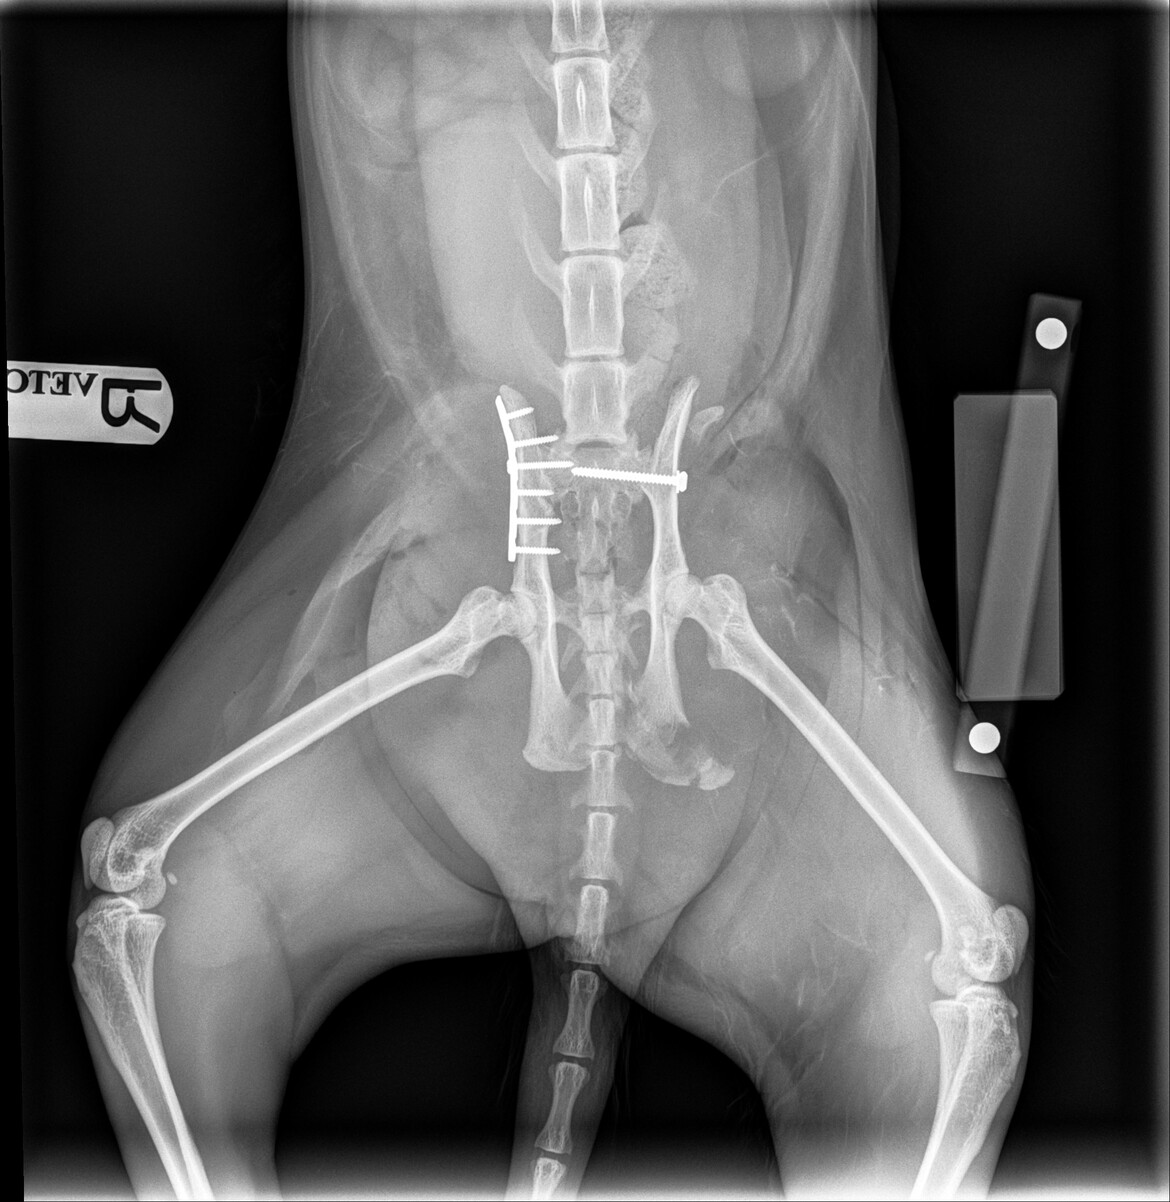

We were told what caused his pelvis to fracture in multiple places is caused by a car hitting him and the scrapes on his other side and butt is caused by the car as well as Miles dragging himself off the road to safety. We were also told his left hind leg has temporary nerve damage which is why he is currently unable to control it much. His pelvis was also DISLOCATED from his spine and needed to be popped back to place.

- Surgery for multiple Fractures on his Pelvis

- X-Rays

X-ray after surgery: